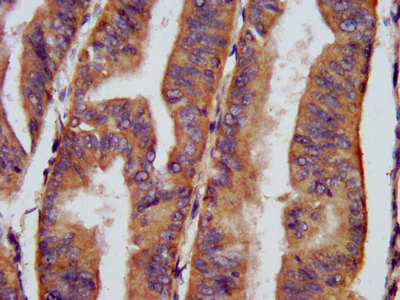

IHC image of CSB-PA005397LA01HU diluted at 1:400 and staining in paraffin-embedded human lung cancer performed on a Leica BondTM system. After dewaxing and hydration, antigen retrieval was mediated by high pressure in a citrate buffer (pH 6.0). Section was blocked with 10% normal goat serum 30min at RT. Then primary antibody (1% BSA) was incubated at 4°C overnight. The primary is detected by a biotinylated secondary antibody and visualized using an HRP conjugated SP system.